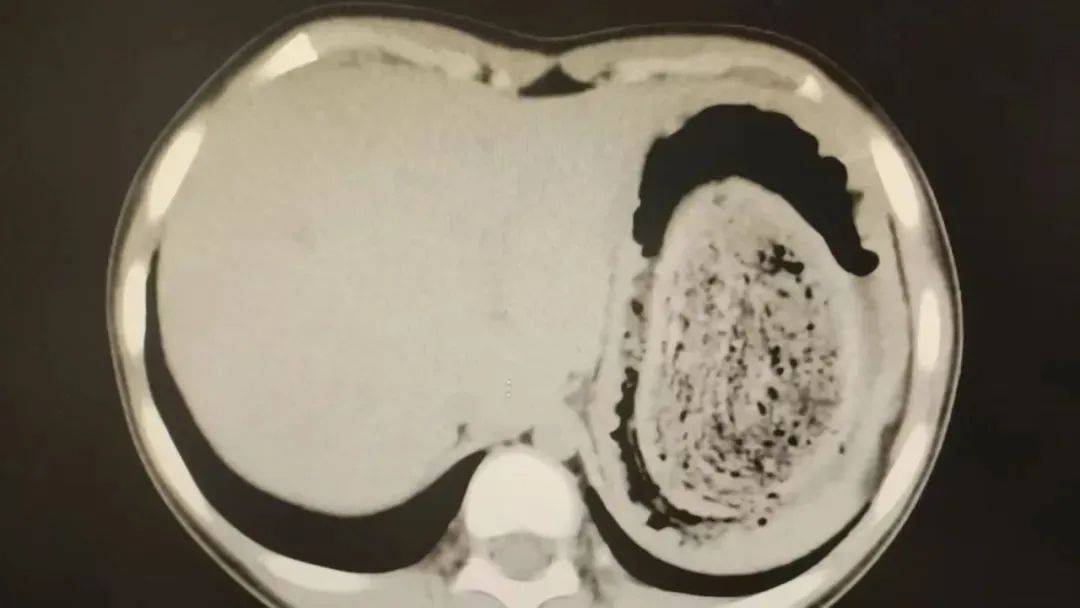

在胃镜帮助下,妮妮胃里的情况逐渐明了苏格兰超级联赛。一个滚圆黑色的毛发球混合着食物残渣占据整个胃腔,这些头发相互缠绕形成一个实心的“发石”,此外胃里还有一个鸡蛋大小的溃疡。

症结找到了,就是这个巨大的发石导致妮妮出现营养不良、贫血和闭经,当务之急就是取出“发石”,给胃进行“大扫除”苏格兰超级联赛。

“发石”混杂着食物残渣,就像一个黑色的小西瓜苏格兰超级联赛。由于整个“发石”体积太大,为避免损伤胃壁,医生借助手术工具将“发石”切割、分解,再小心翼翼地分块取出。整场手术持续2个多小时,最终取出4斤头发碎片。